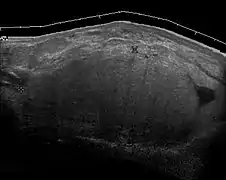

Medical imaging

Medical ultrasonography and magnetic resonance imaging (MRI) of liposarcomas are helpful and often essential in determining their extent, surgical accessibility, and relationship to any observed organ dysfunctions. Since ultrasonography is usually unable to distinguish a liposarcoma from a benign lipoma, MRI is the initial imaging of choice to provide evidence relative to making this distinction.[67]

Fig. 5 Ultrasonography of a liposarcoma with high-echo areas reflected from its lipomatous matrix and low-echo areas reflected from its non-lipomatous areas.[69]

Fig. 5 Ultrasonography of a liposarcoma with high-echo areas reflected from its lipomatous matrix and low-echo areas reflected from its non-lipomatous areas.[69] Fig. 6 Ultrasonography of a liposarcoma mimicking a lipoma. This homogeneous high-echoic mass has the same appearance as a lipoma.[69]